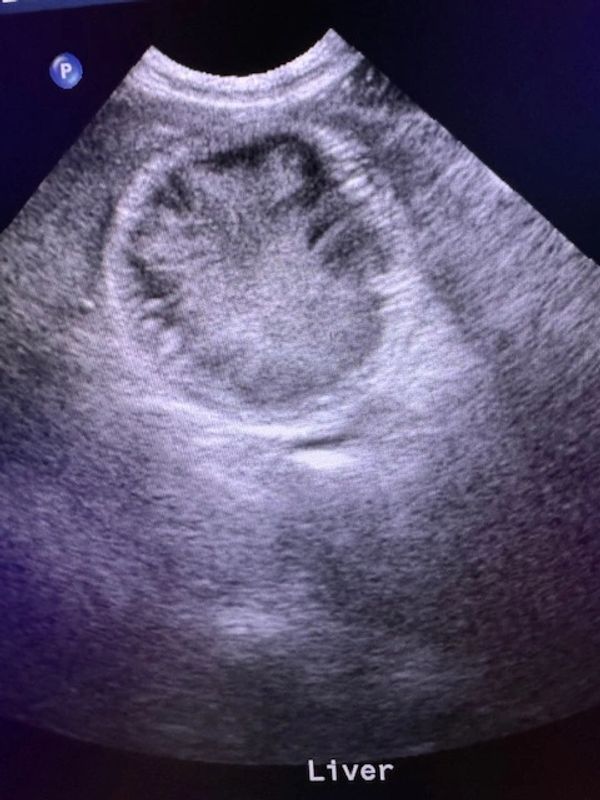

Ultrasound: